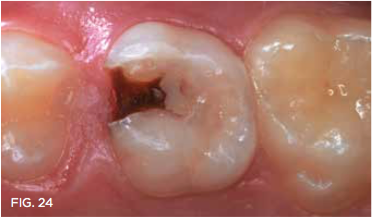

Case 7. Six months prior, this 12-year old was brought to the office for an emergency visit with a fractured a 6-year-old Class II resin-modified glass-ionomer restoration. Subsequently, he complained that the tooth was sensitive to cold stimulus. After one SDF application, sensitivity was relieved and the tooth remained as shown, until it exfoliated within a year (Figure 24).

Fig 24. 12-year-old patient had no tooth sensitivity 6 months after SDF application, and tooth exfoliated a few months later.

Fig 24